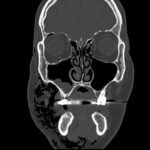

Subcutaneous emphysema (SE) is a rare but significant complication following dental procedures characterized by the presence of air in the subcutaneous tissue. This case report presents a 67-year-old male who developed right-sided facial swelling after tooth extraction, a procedure executed with high-power dental tools. Clinical findings included facial swelling and crepitus with no lip involvement, differentiating SE from an allergic reaction and hematoma. Diagnostic imaging through computed tomography (CT) and chest X-ray confirmed SE, showing diffuse subcutaneous air in facial and neck soft tissues. Initial management in the emergency department (ED) involved administration of antihistamines, corticosteroids, antibiotics, and otolaryngology (ENT) consultation with close monitoring for airway compromise. This case underscores the importance of including SE in differential diagnoses for post-dental procedure swelling, the effectiveness of CT imaging in SE identification, and the importance of early detection and treatment to prevent severe complications like respiratory and cardiac issues.